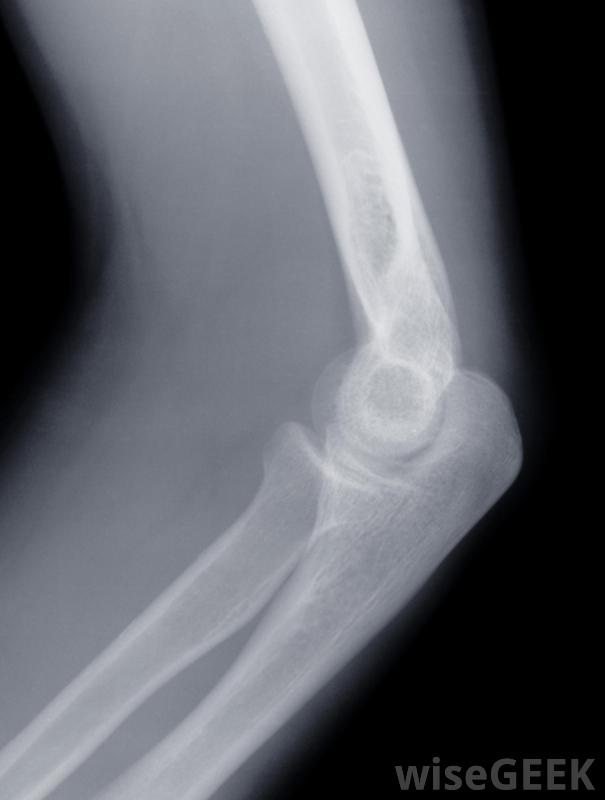

膝盖受伤可能导致膝盖疼痛和肿胀。通常建议休息腿部以减轻膝盖肿胀和疼痛。长时间站立并对膝盖施加压力可能会恶化肿胀和增加疼痛。虽然加热垫可以缓解膝关节疼痛,但不建议使用,因为热会促进肿胀并进一步增加疼痛。当膝盖问题变得慢性时,借助拐杖行走有时可以通过承受腿部重量来减轻膝关节肿胀和疼痛在极少数情况下,当保守的止痛方法无法缓解膝盖肿胀和疼痛时,手术可能是有必要的。膝关节疼痛和肿胀的手术类型取决于引起这种情况的原因。如果症状与软骨有关,则应进行手术移除受伤软骨。如果存在骨刺,移除它们也可以缓解症状。如果膝盖骨因受伤而骨折,则应进行手术修复它可能是唯一的选择,彻底的外科会诊可以为病人提供选择,因此他和他的医生可以决定哪种治疗是合适的